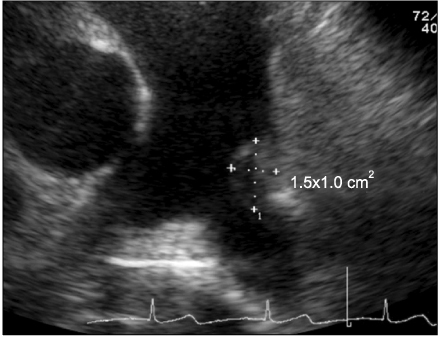

Fig. 2

Transthorasic echocardiography finding. A 1.5×1.0 cm sized vegetation at left pulmonary artery is seen.

Fig. 2 Transthorasic echocardiography finding. A 1.5×1.0 cm sized vegetation at left pulmonary artery is seen.